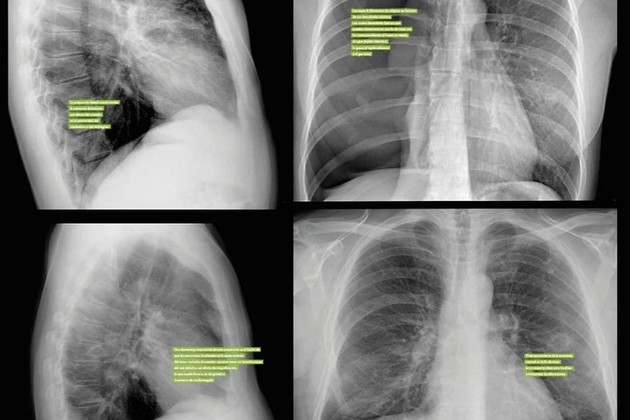

Garay utilizó una base de datos abierta compuesta de 3.851 radiografías de la Universidad de Indiana en Estados Unidos para "entrenar" a la red neuronal.

Garay explicó que, para crear la herramienta, utilizó una arquitectura provista para la descripción de imágenes genéricas y la aplicó al dominio médico para que genere automáticamente el informe médico.

En ese sentido destacó que la ventaja es que "puede reducir el trabajo que lleva a cabo el personal médico, que en lugar de redactar el informe completo se enfocará en revisar y modificar uno generado automáticamente".